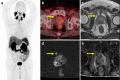

Results: We reviewed 57 original research articles during the period 2016-2021: 14 articles regarding the radiotracer PSMA; 18 articles regarding the primary tumor detection, local tumor staging, managing local recurrence; 17 articles for managing lymph node metastases; and eight articles for managing bone and other distant metastases. PSMA PET could be complementary to mpMRI for primary prostate cancer localization and is particularly valuable for PI-RADS three lesions. PET-MRI is better than PET-CT in local tumor staging due to its specific benefit in predicting extracapsular extension in MRI-occult prostate cancer patients. PET-MRI is likely superior as compared with PET-CT in detecting local recurrence, and has slightly higher detection rates than PET-CT in lymph node recurrence. PET-CT and PET-MRI seem to have equivalent performance in detecting distant bony or visceral metastases.